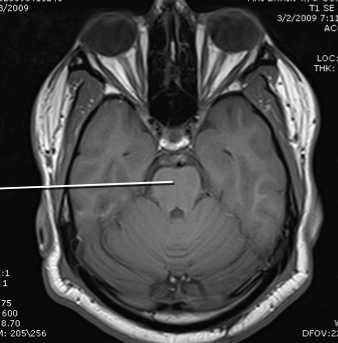

amygdala

hypothalamus

hippocampus

tegmentum and tectum of midbrain